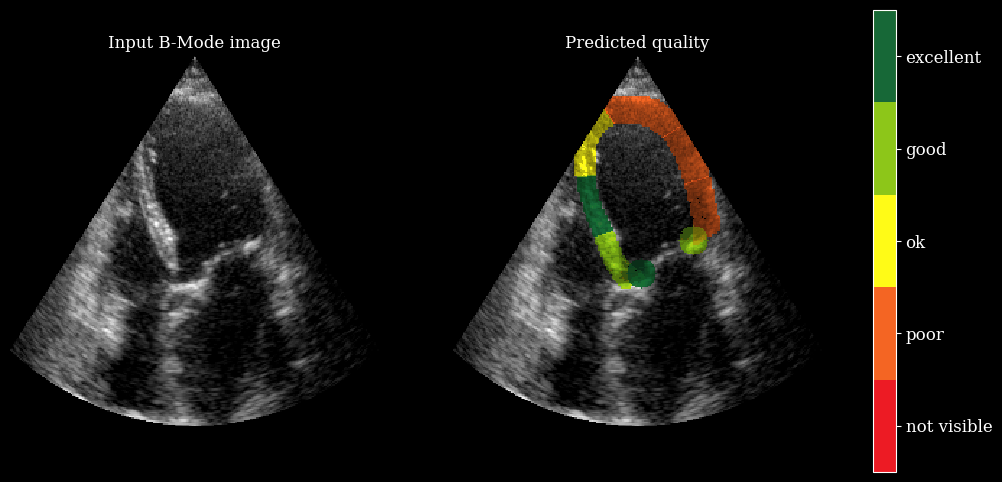

We need the arqee package for a complete visualization. The colored overlay shows the predicted regional image quality for each myocardial region.

import arqee

frames = []

for image, mask, labels in zip(batch_np, masks, scores):

labels = [int(i) for i in labels]

image = np.squeeze(image, axis=-1)

fig, *_ = arqee.plot_quality_prediction_result(image, mask, labels)

frames.append(matplotlib_figure_to_numpy(fig))

plt.close(fig)

save_video(frames, "./myocardial_image_quality.gif", fps=10)

zea: Succesfully saved GIF to -> ./myocardial_image_quality.gif

myocardial image quality